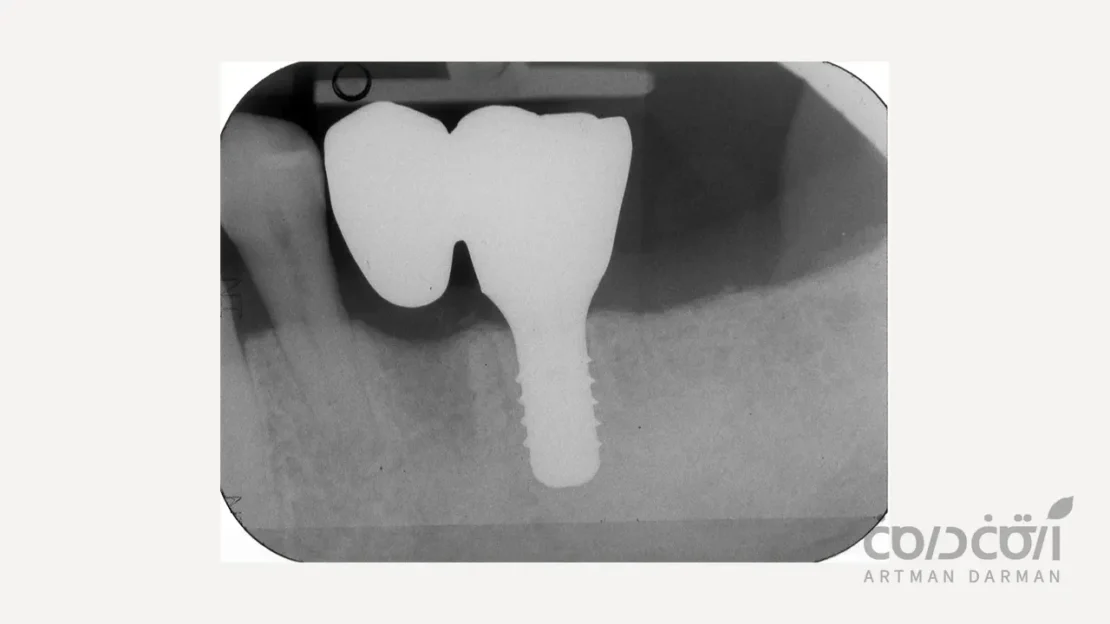

راهکار اول کاشت دو ایمپلنت مجزا به عنوان استاندارد طلایی است

این روش، ایده آل ترین، بیولوژیک ترین و محافظه کارانه ترین راه حل برای جایگزینی دو دندان با ایمپلنت است. در این رویکرد، برای هر دندان از دست رفته، یک ایمپلنت مجزا با روکش مستقل خود کاشته می شود. این روش به دلایل زیر به عنوان استاندارد طلایی شناخته می شود:

تقلید کامل از ساختار طبیعی

این روش دقیقاً آناتومی و عملکرد طبیعی دندان ها را شبیه سازی می کند. هر دندان دارای ریشه (ایمپلنت) و تاج (روکش) مستقل خود است.

توزیع بهینه نیروها

هر ایمپلنت تنها نیروی جویدن وارد بر روکش خود را تحمل می کند و این نیرو به صورت عمودی و فیزیولوژیک به استخوان منتقل می شود. هیچ نیروی اهرمی یا استرس مخربی در کار نیست که این امر پایداری بلندمدت درمان جایگزینی دو دندان با ایمپلنت را تضمین می کند.